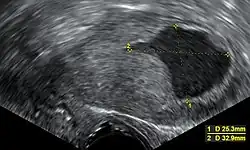

Transvaginal ultrasound to examine the endometrial thickness in women with postmenopausal bleeding is increasingly being used to aid in the diagnosis of endometrial cancer in the United States.[43] In the United Kingdom, both an endometrial biopsy and a transvaginal ultrasound used in conjunction are the standard of care for diagnosing endometrial cancer.[15] The homogeneity of the tissue visible on transvaginal ultrasound can help to indicate whether the thickness is cancerous. Ultrasound findings alone are not conclusive in cases of endometrial cancer, so another screening method (for example, endometrial biopsy) must be used in conjunction. Other imaging studies are of limited use. CT scans are used for preoperative imaging of tumors that appear advanced on physical exam or have a high-risk subtype (at high risk of metastasis).[44] They can also be used to investigate extrapelvic disease.[15] An MRI can be of some use in determining if the cancer has spread to the cervix or if it is an endocervical adenocarcinoma.[44] MRI is also useful for examining the nearby lymph nodes.[15]